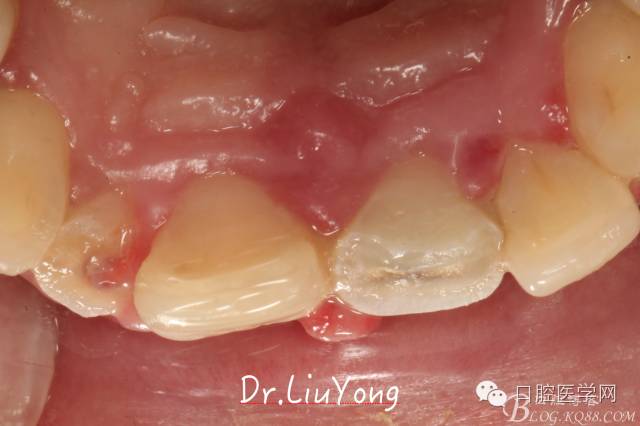

檢查:面部對(duì)稱無腫脹畸形,張口度正常,口內(nèi)檢查可見A2牙冠缺失,可見直徑約1.5mm左右穿髓孔,冷熱刺激痛+,叩痛+,探痛+,近中斷面探診位于齦下1.5mm,A1B1B2松動(dòng)2-3度,B1牙冠缺失1/2,冷熱刺激痛-,叩痛+,B2牙冠完整,A2-B2牙齦紅腫,探診極易出血,全口口腔衛(wèi)生差,牙結(jié)石++,A1B1之間牙齦乳頭紅腫嚴(yán)重,B1唇側(cè)牙齦萎縮明顯,牙齦邊緣可見縫線兩處,局部有滲出,齦緣冠方1mm處見白色骨塊,松動(dòng),觸痛明顯,觸及骨塊時(shí)可見B1及B2近中唇側(cè)牙齦動(dòng)度,B1B2之間唇側(cè)牙齦乳頭缺失,B2近中根面可見大量牙結(jié)石。重度深覆合,牙尖交錯(cuò)位時(shí)C3-D2咬至上前牙腭側(cè)齦緣,A1切端咬至C12唇側(cè)齦緣。其余牙齒未見明顯異常。

術(shù)前口內(nèi)照片如下: